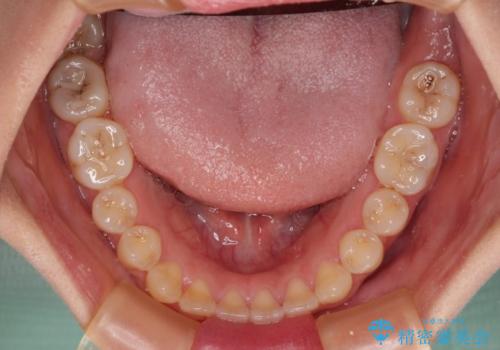

- 前歯の開咬を気にして来院された患者様です。

開咬の治療は、前歯を閉じるように動かすとともに、上下臼歯を圧下(骨内にめり込ませる)させることで進めて行きます。

インビザラインは臼歯の圧下を効果的に行えるため、インビザラインを用いて矯正治療を行うこととしました。